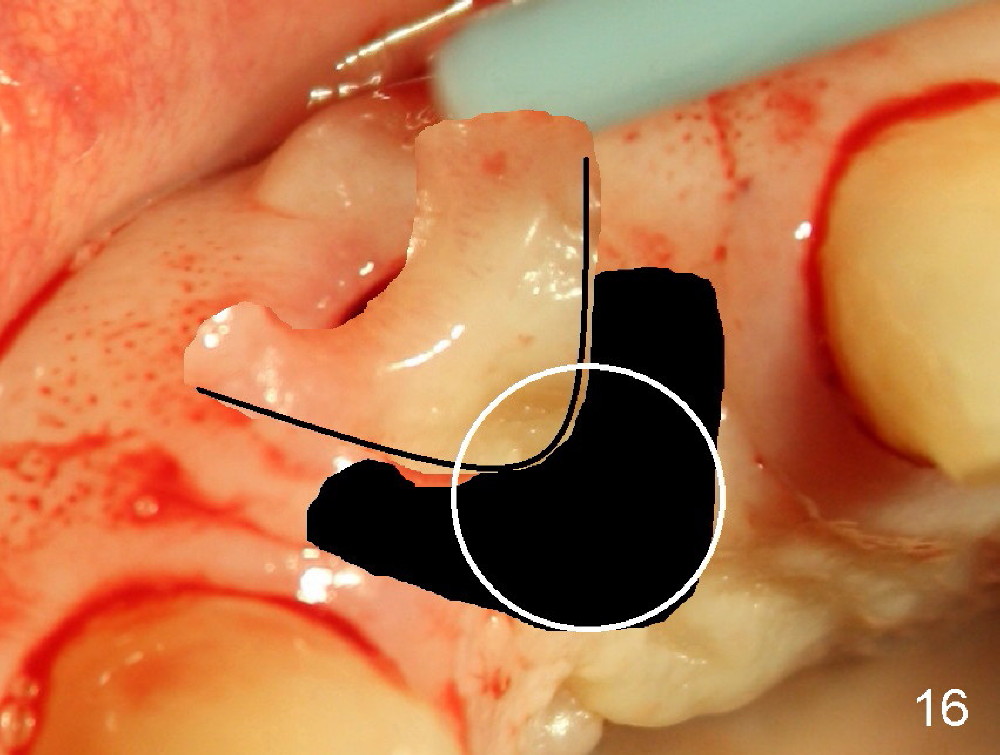

Malpositioned implant in the anterior region is cosmetically unacceptable. Immediate provisional allows us to note the issue immediately. The crown looks too long. Secondly, the provisional is easily dislodged, since the buccal aspect of the angled abutment is over trimmed (Fig.1). The implant (3.8x14 mm), which has been placed 3.5 months, is unexpectedly easily removed by reverse torque (Fig.2). The buccal wall is intact, whereas there seems to be enough bone lingually to place an implant. A small incision is made (Fig.11) so that the gingival tissue can be transferred buccally (Fig.12) and the immediate implant is to be placed palatally (Fig.13 white circle). There is no difficulty forming osteotomy in the palatal wall, followed by inserting 4.5x20 mm tap at the depth of 17 mm (Fig.3,5). But the tap is not palatal enough (Fig.4). By removing more palatal bone, the 4.5x17 implant (Fig.6) appears to be placed palatally enough for restoration (Fig.7; A: abutment; *: buccal gap). The biggest problem is that the palatal flap (Fig.7 arrowheads) cannot be pushed buccally; instead remains palatally. This leads to buccal tissue deficiency (Fig.8). Connective tissue graft is offered, but declined. The patient insists that she has low smile line. Following immediate provisional, mixture of allograft and synthetic graft is placed in the buccal gap (Fig.9). The overbuilt graft is held in place by perio dressing.

If a larger incision were made (Fig.14) and the flap were dissected freely (Fig.15), the buccal tissue deficiency would be less (Fig.16). Follow up is shown 2 3.